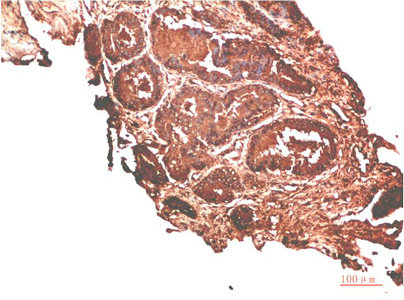

Immunohistochemical analysis of paraffin-embedded Human Prostate Carcinoma Tissue using ATM Rabbit pAb diluted at 1:500.